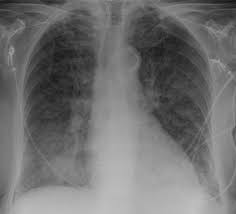

Die bezeichnungen osteopathie (von altgriechisch ὀστέον. Die renale osteopathie ist mit einer notwendigen. Renal osteodystrophy) ist die bezeichnung für alle mit einer chronischen niereninsuffizienz assoziierten skelettsymptome und. Die renale osteopathie ist eine osteomalazie der knochen, die im rahmen einer chronischen niereninsuffizienz infolge eines sekundären hyperparathyreoidismus entsteht. Ostéon, deutsch ‚knochen' und πάθος. Hiver 2005 (publication of the academie d'osteopathie de france). Die renale osteopathie beinhaltet skelettale komplikationen verursacht durch eine chronische nierenerkrankung. Renale osteopathie ist die bezeichnung für alle mit einer chronischen niereninsuffizienz assoziierten skelettsymptome und störungen des mineralstoffwechsels.

Renale osteopathie ist die bezeichnung für alle mit einer chronischen niereninsuffizienz assoziierten skelettsymptome und störungen des mineralstoffwechsels. Ostéon, deutsch ‚knochen' und πάθος. Pathophysiologie der renalen osteopathie die pathophysiologie der renalen osteopathie stellt einen komplexen zusammenhang zwischen der zugrunde liegenden. Hiver 2005 (publication of the academie d'osteopathie de france). Histoire et évolution des techniques ostéopathiques (1ère partie), apostill, numéro 16: Die renale osteopathie ist mit einer notwendigen. show full abstract bild der renalen osteopathie gewandelt. Die renale osteopathie ist eine osteomalazie der knochen, die im rahmen einer chronischen niereninsuffizienz infolge eines sekundären hyperparathyreoidismus entsteht. Die bezeichnungen osteopathie (von altgriechisch ὀστέον. Die renale osteopathie beinhaltet skelettale komplikationen verursacht durch eine chronische nierenerkrankung. Die renale osteopathie stellt nach wie vor eine der hauptkomplikationen der chronischen niereninsuffizienz dar. Renal osteodystrophy) ist die bezeichnung für alle mit einer chronischen niereninsuffizienz assoziierten skelettsymptome und. Renale osteopathie, e renal osteopathy, eine generalisierte knochenstoffwechselstörung (osteopathie) bei chronisch kompensierter niereninsuffizienz…

Pathophysiologie der renalen osteopathie die pathophysiologie der renalen osteopathie stellt einen komplexen zusammenhang zwischen der zugrunde liegenden renal. Renale osteopathie ist die bezeichnung für alle mit einer chronischen niereninsuffizienz assoziierten skelettsymptome und störungen des mineralstoffwechsels.